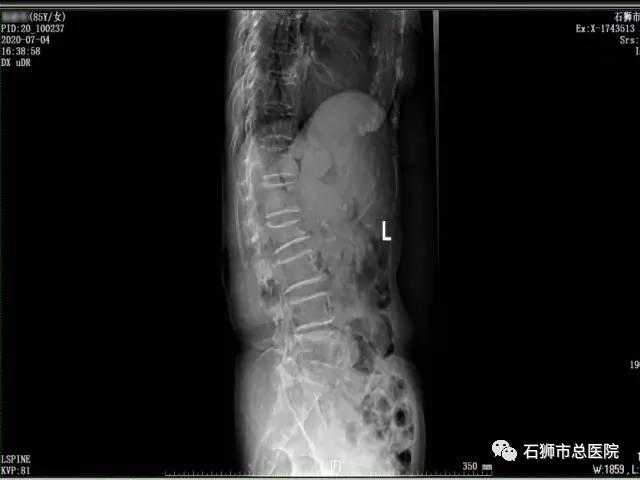

患者,女,89岁,以"摔伤致腰背部肿痛,活动受限5天"为主诉入院。入院诊断:1.腰2椎体压缩性骨折;2.骶椎骨折,3.高血压病(2级高危)。

考虑患者近九十岁高龄,常规手术风险难以耐受,且椎体后壁破碎,手术风险极高,经科室内讨论,拟行经皮椎体球囊扩张成形术,术中为进一步减少手术时间,减少手术风险,降低骨水泥经后壁进入椎管风险,予改良行单侧经皮椎体球囊扩张成形术。

术后患者恢复良好,指导功能锻炼,早期腰背支具辅助下起床活动,有效避免了患者卧床并发症的发生。

手术 · 前

手术 · 后

腰椎骨折